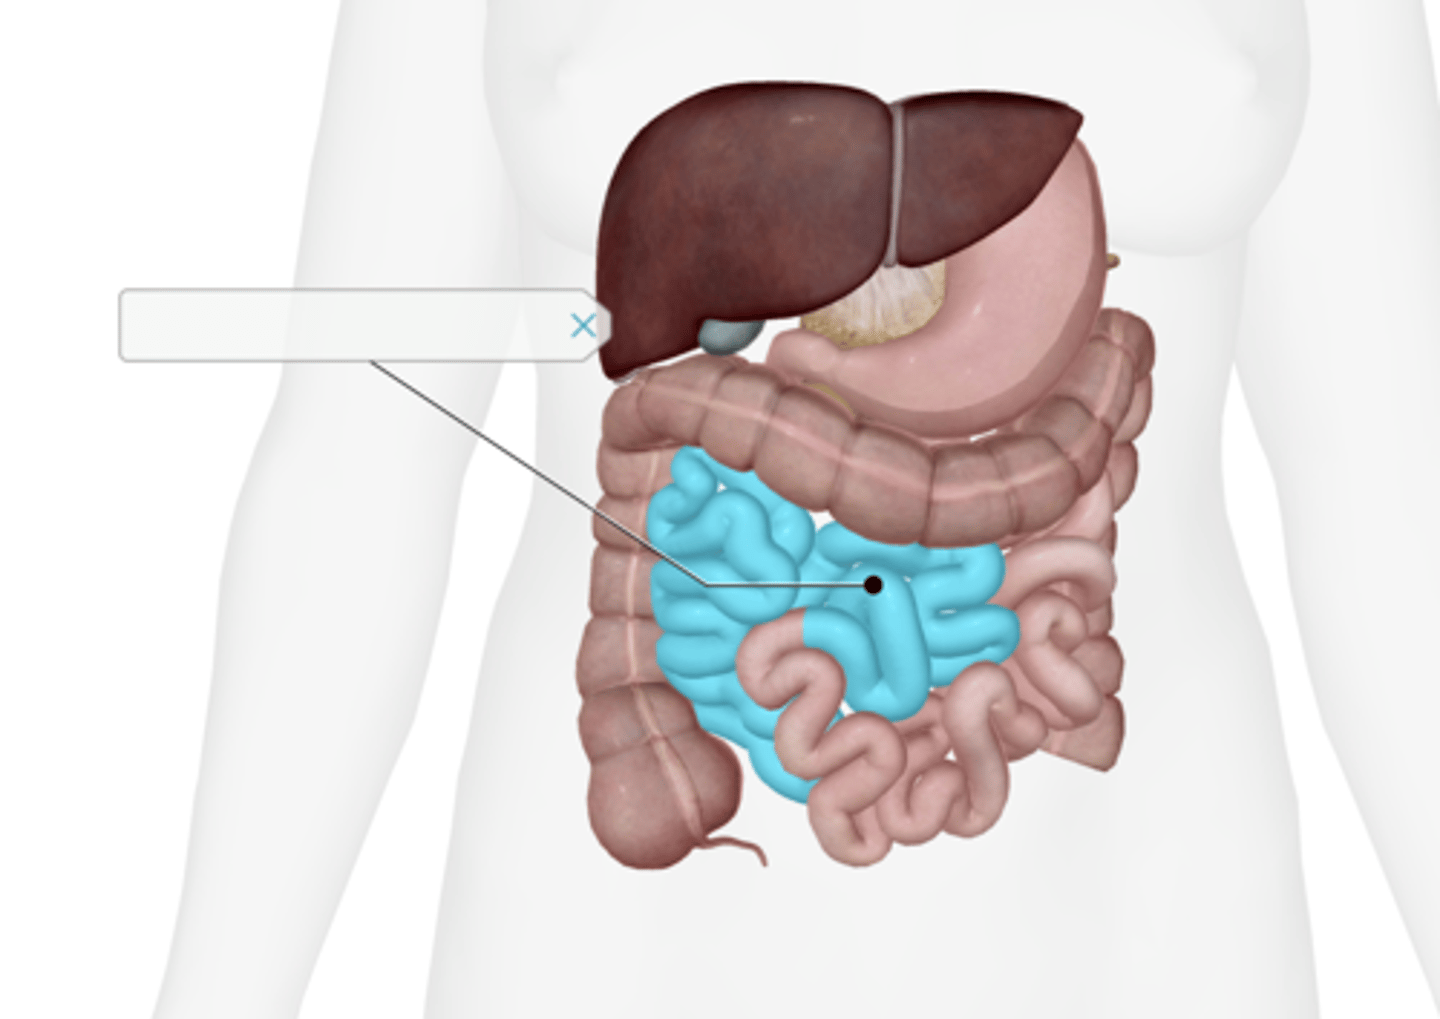

Jejunum

Ileum

Taenia coli

(only partially selected)

Superior mesenteric artery

Inferior mesenteric artery

Cecum

Appendix